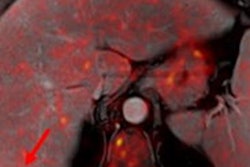

The high field, dry magnet system is designed for medical research related to inflammation, oncology, and nephritis. Researchers at UiT intend to use the scanner for advanced research into gliomas and other conditions.

The 7-tesla PET/MRI scanner. Image courtesy of MR Solutions.The system enables PET and MRI images together or separately for both soft-tissue contrast and molecular imaging, and it features a large axial 15-cm field-of-view with the PET module and a 24 cm bore with MRI alone, according to the vendor.